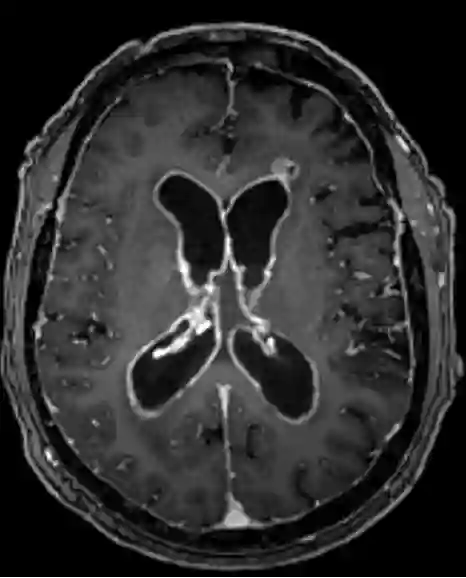

Ventrikulitis MRT

Axiale T1 MRT Sequenz mit Kontrastmittel eines Patienten mit einer ausgeprägten Ventrikulitis.